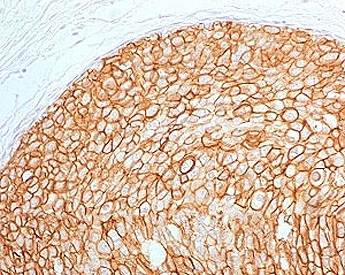

IHC testing of FFPE human breast carcinoma with ErbB2 antibody (clone 2KRI7-2). HIER: boil tissue sections in pH6, 10mM citrate buffer, for 10-20 min followed by cooling at RT for 20 min.

Applications Immunohistochemistry (FFPE) : 1-2ug/ml